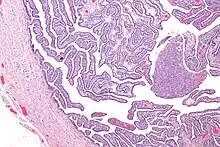

Definitive criteria include histopathologic evidence of endometritis, thickened filled Fallopian tubes, or laparoscopic findings. Gram stain/smear becomes definitive in the identification of rare, atypical and possibly more serious organisms.[24] Two thirds of patients with laparoscopic evidence of previous PID were not aware they had PID, but even asymptomatic PID can cause serious harm.